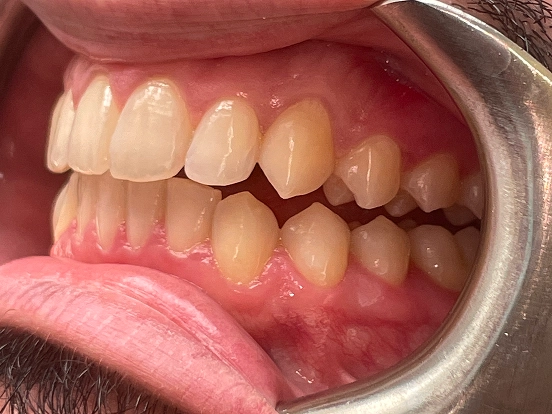

Invisalign DT

DT’s transformation with Invisalign is a perfect example of how advanced orthodontic technology can deliver incredible results. The clear aligners gradually corrected the alignment and bite issues, creating a straighter, healthier, and more attractive smile—all without noticeable brackets or wires.